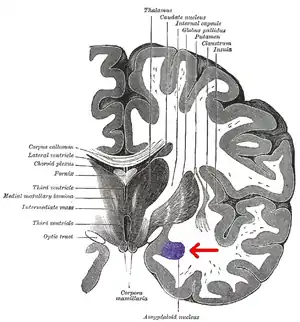

Location of the amygdalae in the human brain

Human brain in the coronal orientation. Amygdalae are shown in dark red.

Coronal section of brain through intermediate mass of third ventricle. Amygdala is shown in purple.